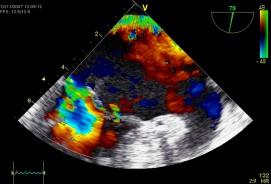

Echokardiografie: LEVÁ KOMORA bez dilatace a hypertrofie, s normální systolickou funkcí a regionální kinetikou kromě D shape, EF LK 55-60%. Diastolická funkce: porucha relaxace LK. PRAVÁ KOMORA FAC PK 18%, TAPSE 13 mm, Vt 9 cm/s, dilatace a hypertrofie PK, těžká prekapilární PH, odhadovaný PASP 90 mmHg, MPAP 55 mmHg, malý perikardiální výpotek

Echokardiografie: LEVÁ KOMORA bez dilatace a hypertrofie, s normální systolickou funkcí a regionální kinetikou kromě D shape, EF LK 55-60%. Diastolická funkce: porucha relaxace LK. PRAVÁ KOMORA FAC PK 19%, TAPSE 17 mm, Vt 9 cm/s, dilatace a hypertrofie PK, těžká prekapilární PH, odhadovaný PASP 130

mmHg, perikardiální výpotek